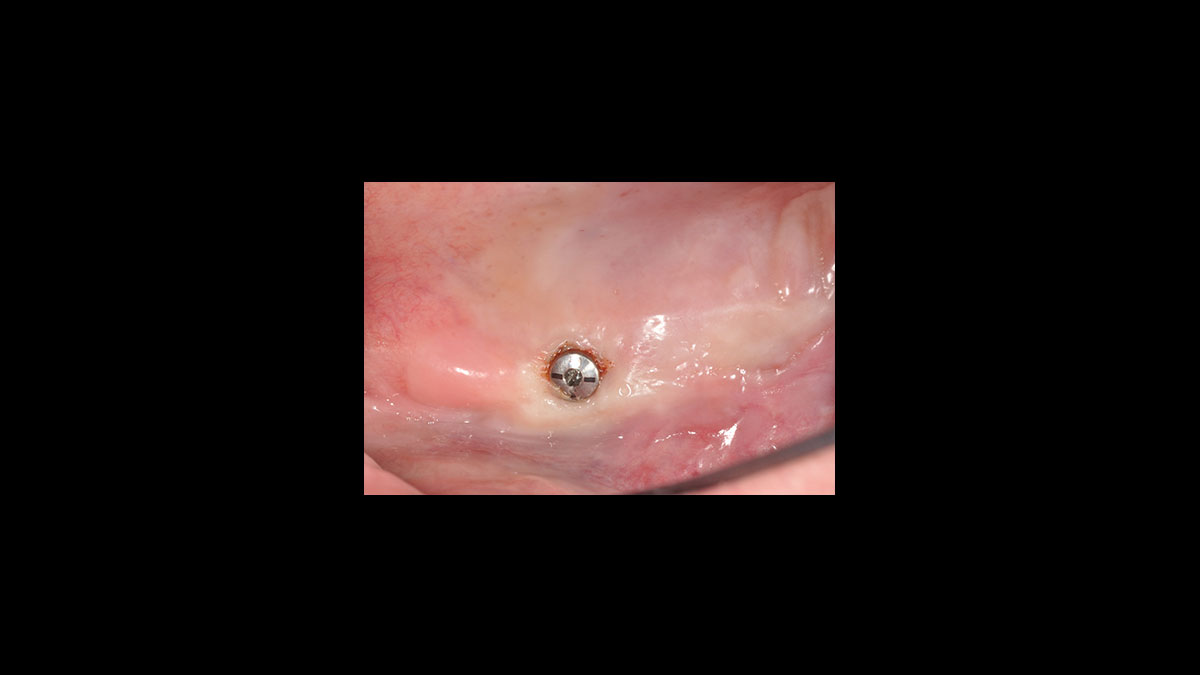

Implant uncovery